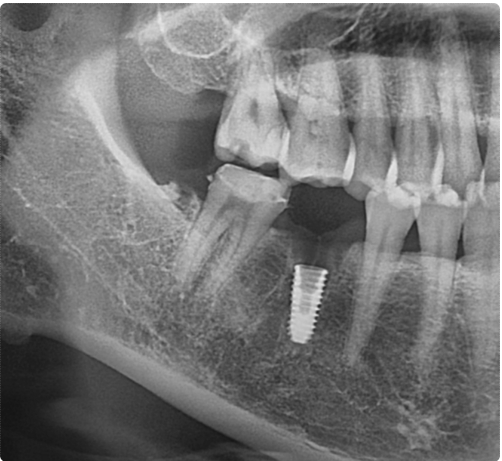

이미 손상이 많이 진행된 상황이어서 치아를 보존하기는 어려웠고, 결국 발치 후 임플란트 치료를 계획하게 되었습니다.

이처럼 비슷한 시기에 내원하셨고 초기 상황도 크게 다르지 않았지만,

한 분은 크라운치료로 치아를 살릴 수 있었고, 다른 한 분은 발치 후 임플란트 치료까지 이어지게 되었습니다.